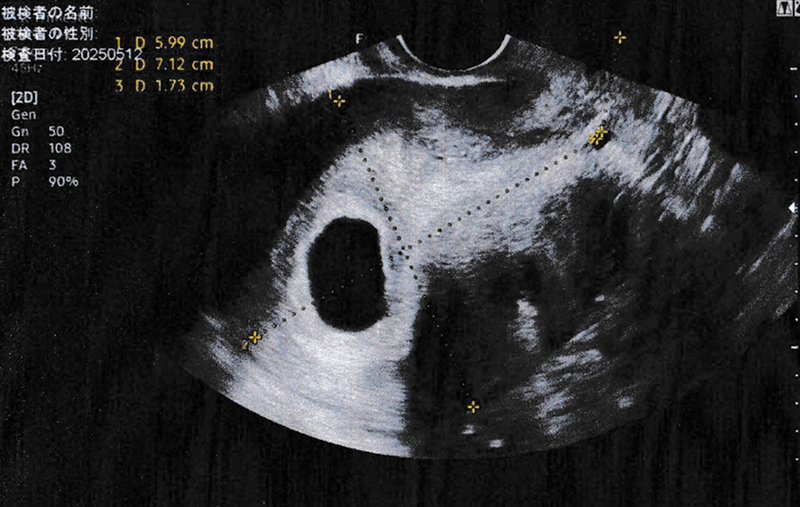

妊娠5週目のエコー画像。

そんな中、4月から始めた妊活の最初の妊娠は流産だった。詳しくは妊娠初期に一定の確率で発生すると言われている稽留流産。ちなみに、稽留流産というのは本来妊娠5~6週目あたりで確認できるはずの胎児の心拍が確認できずに成長が止まってしまう事。

妊娠5週目の診察時に「もしかしたら流産かもしれない。」という話を聞いて、まさかとは思ったけど、その後調べに調べ上げて再診にかかったらそのまさかだったという流れ。